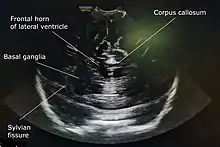

Cranial ultrasound is a technique for scanning the brain using high-frequency sound waves. It is used almost exclusively in babies because their fontanelle (the soft spot on the skull) provides an "acoustic window". A different form of ultrasound-based brain scanning, transcranial Doppler, can be used in any age group. This uses Doppler ultrasound to assess blood flow through the major arteries in the brain, and can scan through bone. It is not usual for this technique to be referred to simply as "cranial ultrasound". Additionally, cranial ultrasound can be used for intra-operative imaging in adults undergoing neurosurgery once the skull has been opened, for example to help identify the margins of a tumour.[1]

A 5 to 7.5 MHz probe is used to scan deeper structures in the brain. A 7 to 12 Mhz probe is used for scanning superficial structures for detecting lesions between the brain and the skull, superior sagittal sinus thrombosis, cerebral oedema, and evaluating the structures of sulci and gyri.[4]

A water-based gel is applied to the infant's head, over the anterior fontanelle, to aid conduction of ultrasound waves. Ideally scans are performed during sleep or when the infant is calm. The operator then uses an ultrasound probe to examine the baby's brain, viewing the images on a computer screen and recording them as necessary.

A standard cranial ultrasound examination usually involves recording of approximately 11 views of the brain from different angles, six in the coronal plane and five in the sagittal and parasaggital planes.[7] This allows all parts of the ventricles and most of the rest of the brain to be visualised.